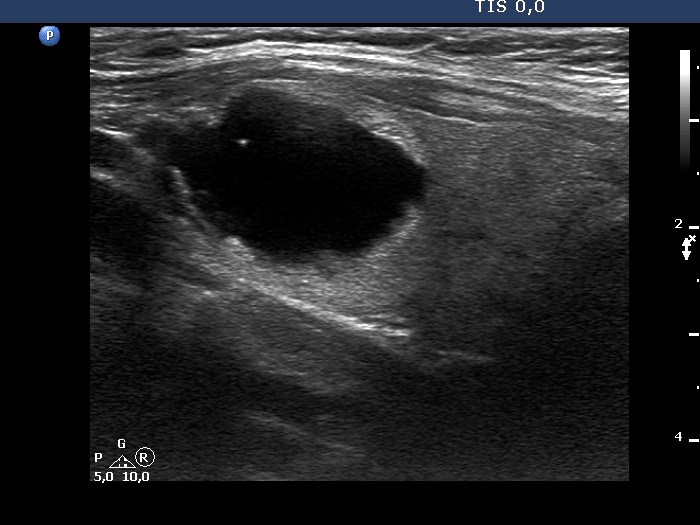

The composition of the nodule - case 1530

Examination 3 years later (ultrasonographic picture 7)

Left lobe, longitudinal scan.